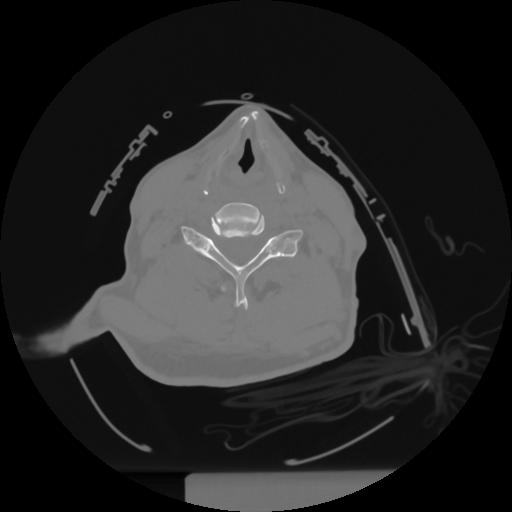

12 P.BLANDAS,,Vol,0.5,P.BLANDAS,,